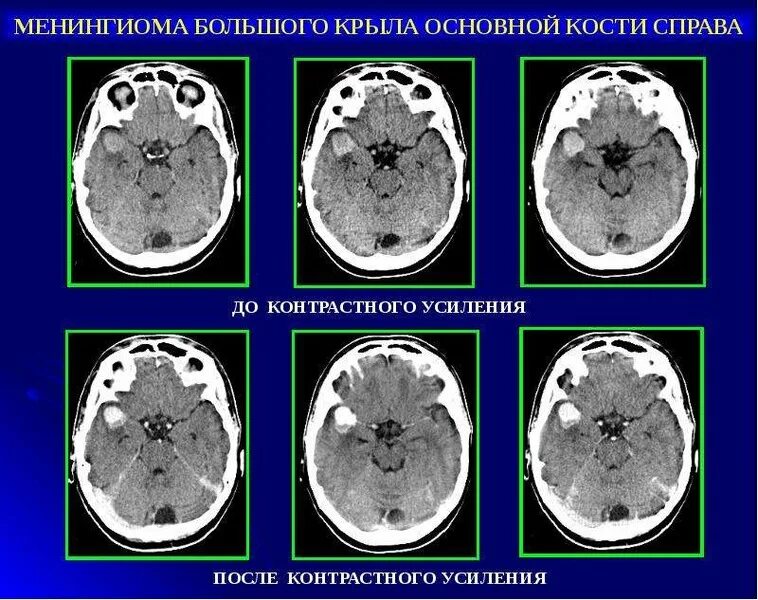

Метастазы в головном мозге мкб